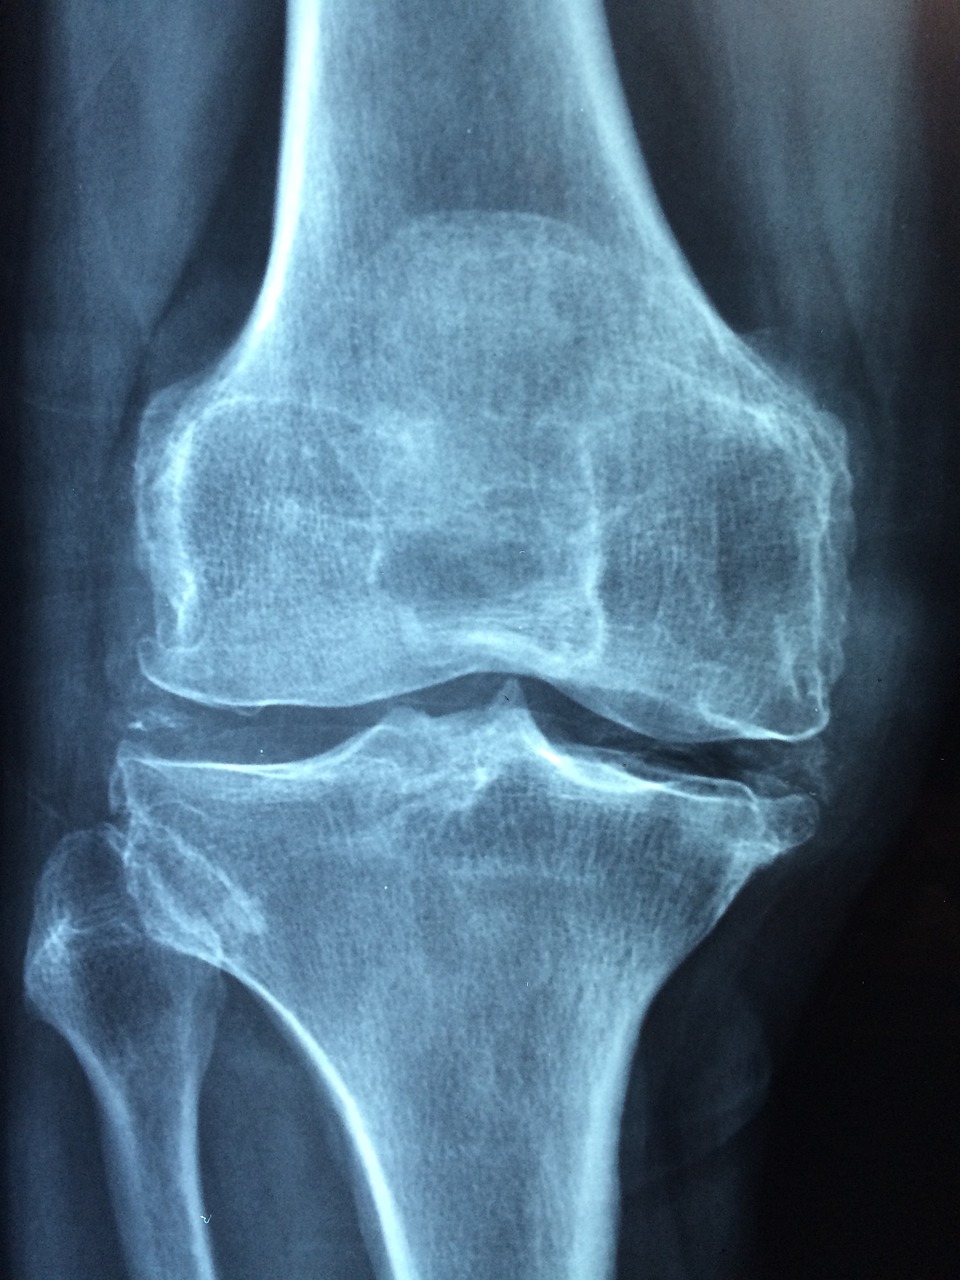

무릎 연골 손상시 치료방법

검진을 통해 무릎 연골이 손상된 것을 확인했다면 보존적 치료인 ✅약물 치료 ✅주사 치료 ✅ 물리 치료 등으로 치료하지만 이보다 심할 경우에는 수술이 불가피할 수도 있습니다.

관절 내시경 수술을 통해 절개 후 내시경과 수술 기구를 통해 직접 무릎을 확인하면서 시행하는 수술을 진행할 수도 있는데요 이럴 경우 3~5일가량 회복 기간이 필요합니다.